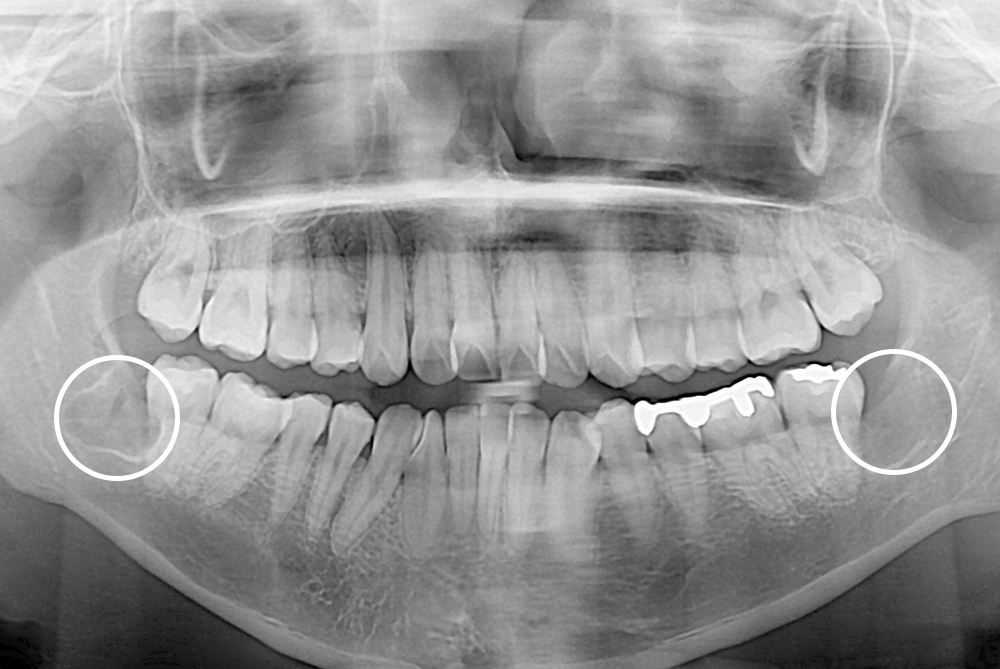

[사랑니] 매복 사랑니 발치

치료전 : 2019-04-18

세종치과는 구강악안면외과학 박사이신 원장님이 발치하는 치과입니다.